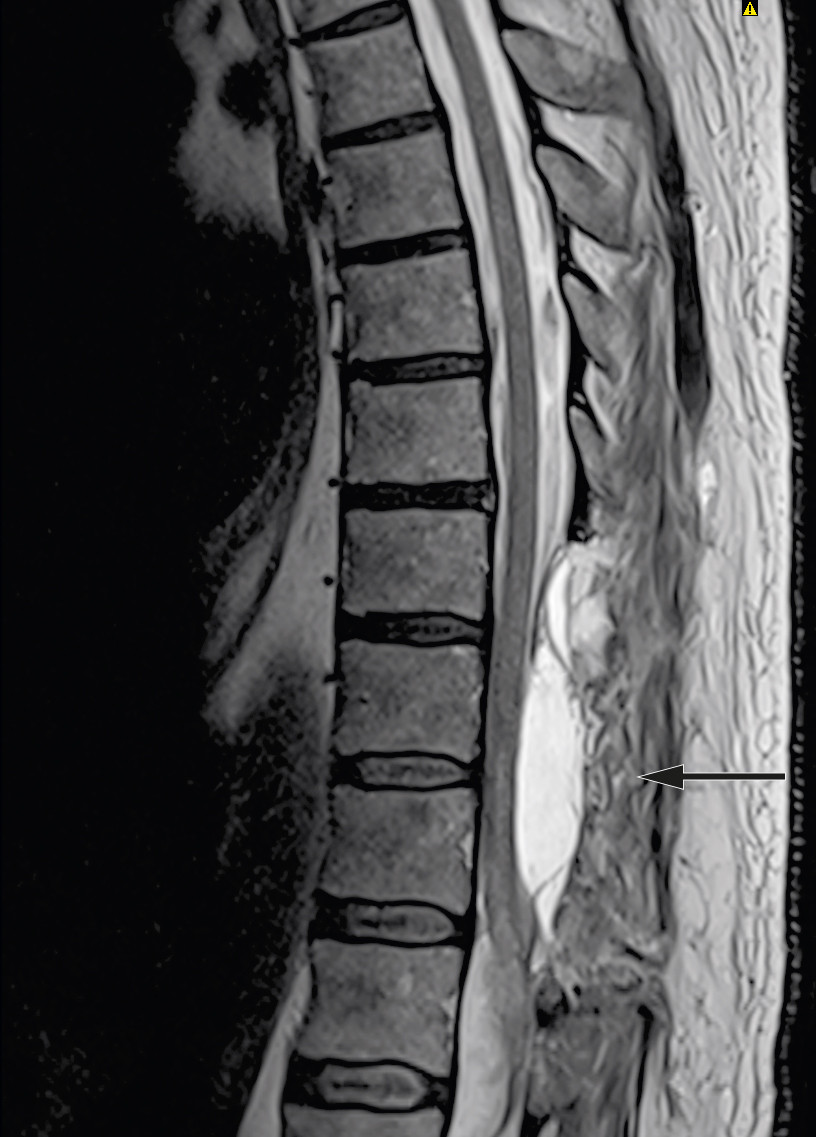

The patient was signed up for emergency surgery under general anaesthesia. The knee-elbow position was used, along with X-ray imaging, midline incision and three-level laminectomy. No epidural haematoma was seen during the surgery, but the blue discoloured dura mater was opened. The subdural haematoma was gently evacuated, and there was no major source of bleeding or difficulty in achieving haemostasis. The spinal cord showed bluish discolouration, and significant subarachnoid and intramedullary haemorrhage was suspected. Closure was then performed under good haemostasis. Postoperative MRI showed a reduced subdural haematoma at laminectomised levels Th9–11, unchanged subdural haematoma at level Th12, new intramedullary signal changes at Th10–L1, and subarachnoid blood caudal to Th12 (Figure 2).